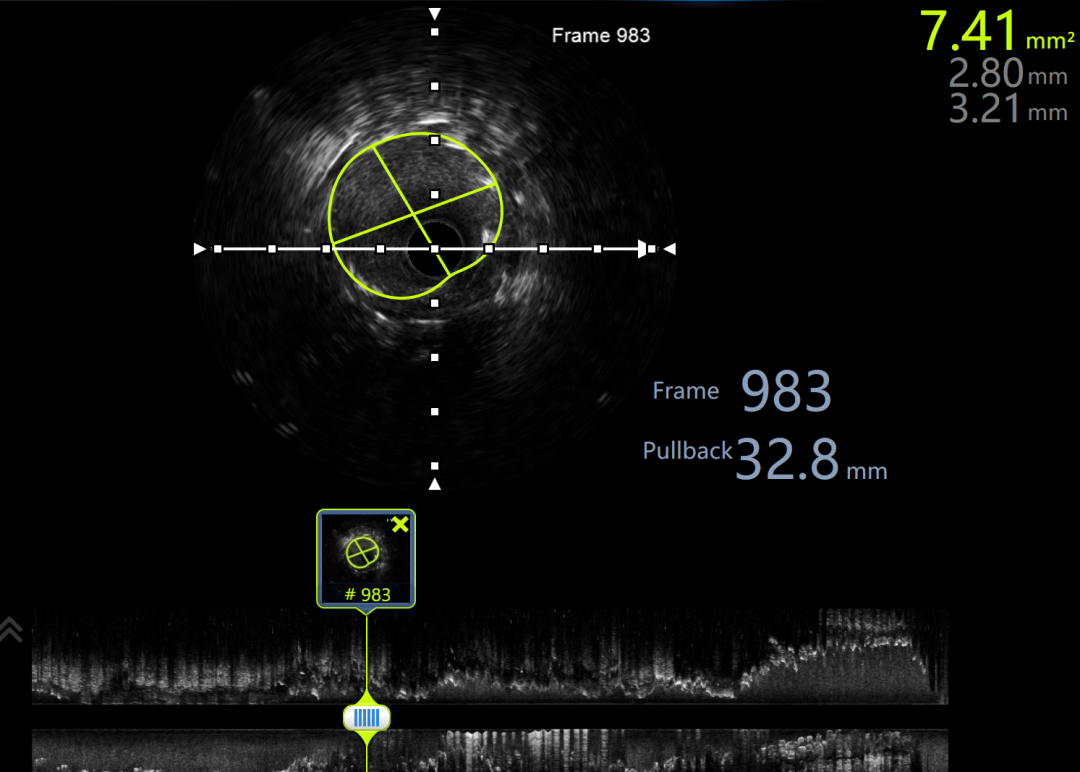

建立轨道后,交换为Runthrough 导丝后,行IVUS检查证实导丝位于血管真腔。

利用IVUS精确选择支架落脚点。

IVUS显示支架贴壁良好,未见夹层,RCA中远段MSA 7.41mm²,术毕。